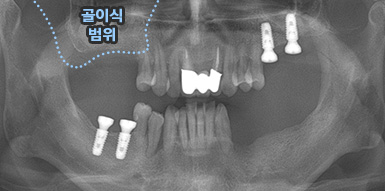

상악동 거상술

상악동 거상술 고난이도 뼈이식술 입니다.

청담네오플란트에서는 상악동 거상술을 비롯한

고난이도 임플란트 시술 노하우가 풍부한 치의학 박사

전문의가 직접 상악동 거상술을 시행합니다

상악동은 윗턱뼈 내부의 구조물로서 개개인에 따라 생김새가 다릅니다.

상악동의 바닥이 잇몸뼈 방향으로 많이 내려온 경우, 임플란트를 식립하기에

잇몸뼈가 부족하게 됩니다. 이러한 경우 상악동 내부로 뼈이식을 하는

상악동 거상술이 필요하게 됩니다.

B

A